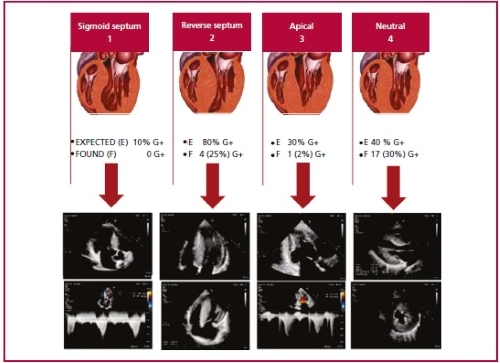

Genotype-phenotype correlation

According to Maron’s

classification, the most frequent forms of presentation were type 1 and type 3

(septal and anterolateral involvement, respectively),

with more G+ detected in type 1 in HCM (9, 75%) and in type 3 in phenocopies (13, 68.4%), p<0.001.

Lever´s classification into 2 and 4

(reverse curvature septum and neutral septum, respectively) was useful when

assessing the likelihood of having G+ based on the anatomical phenotype

expressed by the patient (Table 2 and Figure 4).

Color Doppler echocardiography image from own source.

Figure modified from Lever HM, Karam RF, Currie PJ,

Healy BP. Hypertrophic cardiomyopathy in the elderly. Distinctions from the

Young based on cardiac shape. Circulation 1989; 79(3):580-9.

Fig. 4. Hypertrophy patterns according to the classification of Lever et al.

Pretest probability for a positive genetic testing result according to the

anatomical subtype.